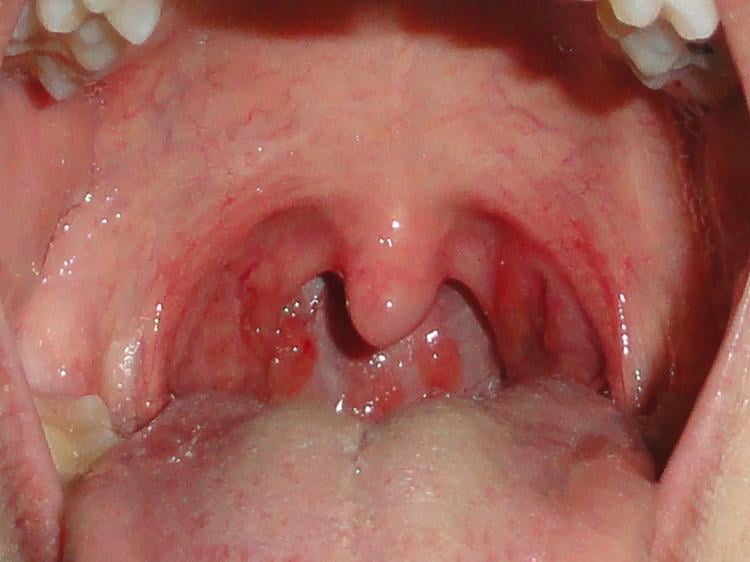

- Amígdalas rojas e inflamadas

Representa solo el 30% de todas las infecciones relacionadas con la garganta. Este tipo de amigdalitis es excepcional en niños menores de 3 años. Se caracteriza por presentar fiebre elevada, intenso dolor de garganta, mal aliento y las famosas “placas de pus” sobre las amígdalas. En este caso si es necesario el uso de antibiótico que puede durar hasta 10 días.

Representa sólo una porción pequeña de los casos de afecciones en la garganta y se trata de una infección de tipo bacteriana. Si no se trata a tiempo puede desencadenar complicaciones como inflamación en los riñones y fiebre reumática que luego ocasiona dolor en las articulaciones. Aunque es una enfermedad que suele afectar a niños, también puede atacar a personas de cualquier edad. Entre los síntomas se muestran amígdalas enrojecidas e inflamadas con rastros de pus, ganglios del cuello inflamados, erupción cutánea y fiebre.